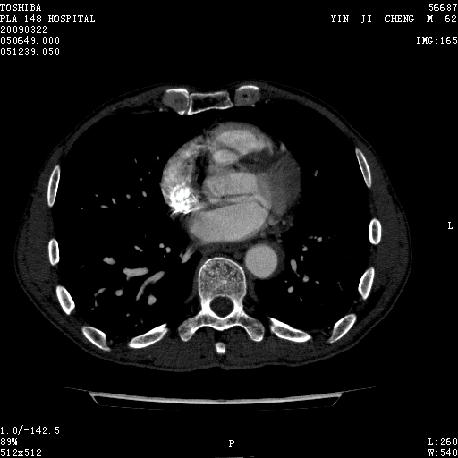

男 62 夜间突然腹痛并向背部放射 ,急诊疑胰腺炎 ,胰淀粉酶正常 ,ct示胰腺未见明显异常,发现降主动脉密度欠均,做主动脉造影示胸腹主动脉半月形低密度充盈缺损,内膜钙化并内移,累及腹腔干致根部明显狭窄,未见明显破裂口。 本人为是不典型夹层,其他人有说是动脉硬化或动脉炎的。请大家发表一下看法。

大动脉炎,左侧房室缺血.

不象夹层,延时扫可鉴别。